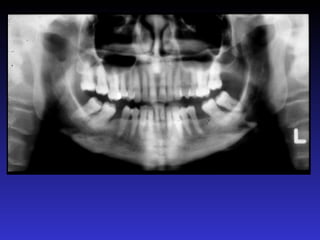

2. Các mốc giải phẫu trên phim toàn cảnh

1. Xoang hàm

2. Hố chân bướm hàm

3. Xương chân bướm

4. Gai bướm

5. Cung xương gò má

6. Lồi khớp xương thái dương

7. Đường khớp gò má thái dương

8. Mỏm gò má

9. Lỗ ống tai ngoài

10. Mỏm chũm

11. Hố sọ giữa

12. Bờ viền ngoài ổ mắt

13. Bờ dưới ổ mắt

14. Lỗ dưới ổ mắt

15. Ống dưới ổ mắt

16. Hốc mũi

17. Vách ngăn mũi

18. Gai mũi trước

19. Xương cuốn dưới

20. Lỗ răng cửa

21. Vòm miệng cứng

22. LồI củ xương hàm trên

23. LồI cầu

24. Mỏm vẹt

25. Khuyết sigma

26. Hố giữa khuyết sigma

27. Mỏm trâm

28. Cột sống cổ

29. Gờ chéo ngoài

30. Ống răng dưới

31. Lỗ ống răng dưới

32. Gai Spix

33. Lỗ cằm

34. Hố tuyến dưới hàm

35. Gờ chéo trong

36. Hố cằm

37. Gờ cằm

38. Gai cằm

39. Xương móng